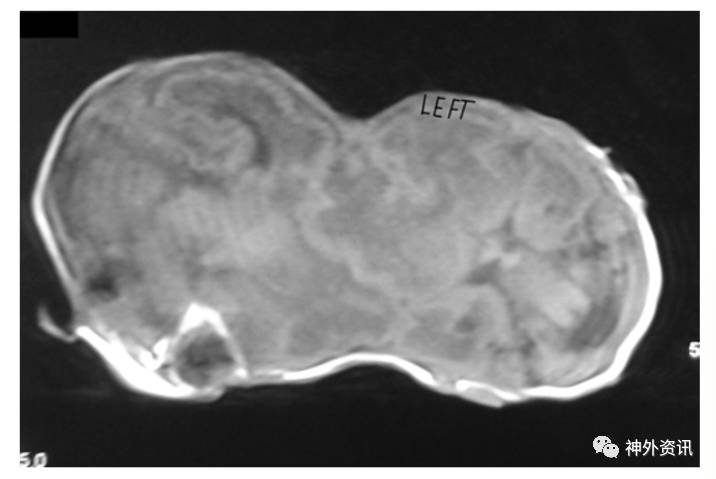

图2. MRI-T1加权像示,左侧婴儿脑结构相对正常,右侧婴儿脑室轻度扩大伴结构异常;两脑间结构有交叉。